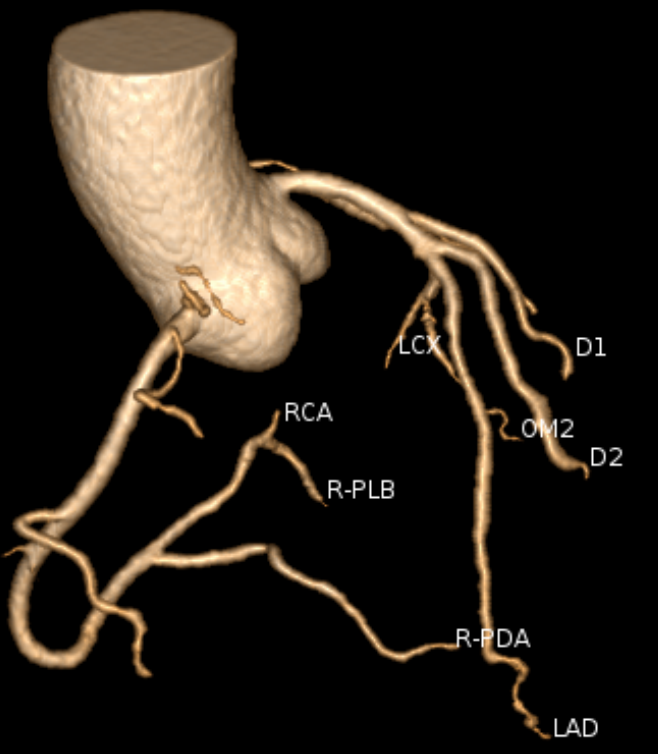

注射少量碘造影剂后,通过CT扫描,计算机能把心脏血管的走行、分支、狭窄处重建出一张高清的3D立体图像。

(1)无创诊断冠心病“金标准”:对冠状动脉显著狭窄(≥50%)的诊断敏感度、特异度均超90%,阴性预测值接近99%——检查结果正常,基本可排除冠心病,避免不必要的有创造影,减少患者痛苦与风险;

(2)揪出“隐形杀手”易损斑块:不仅能判断血管狭窄程度,更能精准识别钙化斑块、非钙化斑块(软斑块)、混合斑块,尤其是易损斑块。这类斑块看似稳定,却可能突然破裂引发急性心梗,是猝死的核心隐患,而传统检查难以发现,CTA能提前3-5年锁定风险;

(3)术后随访“好帮手”:可评估冠脉支架术后通畅性、搭桥术后血管桥形态,为术后干预方案调整提供精准依据。